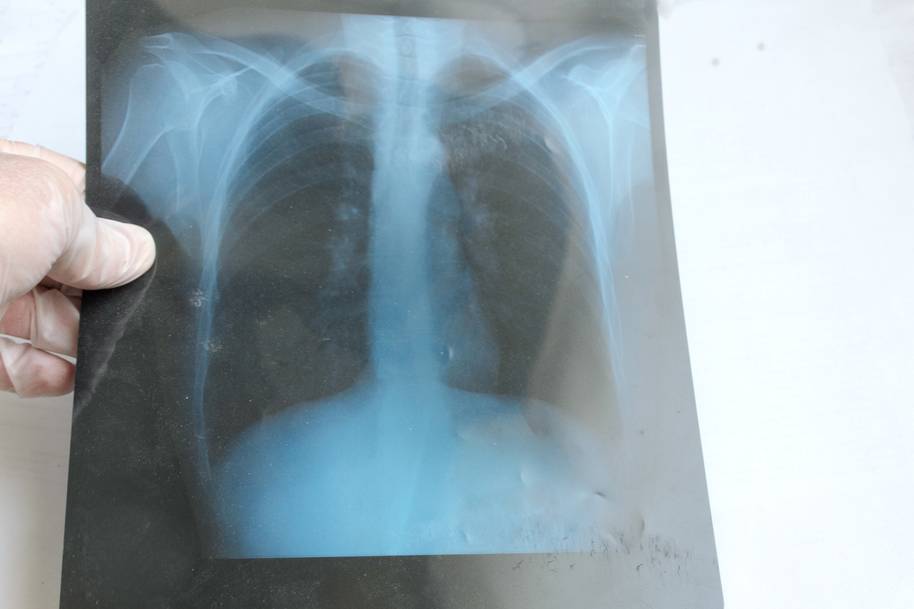

Одной из рекомендуемых врачами ежегодных процедур является посещение кабинета флюорографии. Это позволяет на ранней стадии выявить различные заболевания органов дыхания.

Теперь диагностика стала еще более доступной для жителей Московской области – у них появилась возможность записываться на нее самостоятельно. Раньше это мог сделать только медработник.

Пройти флюорографию можно в поликлинике по месту прикрепления. Записаться на нее можно по тел. 122, через портал госуслуг «Здоровье», инфомат в поликлинике. Диагностика выполняется бесплатно, по полису ОМС.